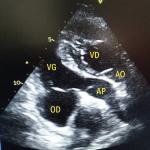

Transposition des gros vaisseaux congénitalement corrigée

Un homme de 39 ans consulte pour une dyspnée d’effort apparue progressivement et des palpitations intermittentes. L...